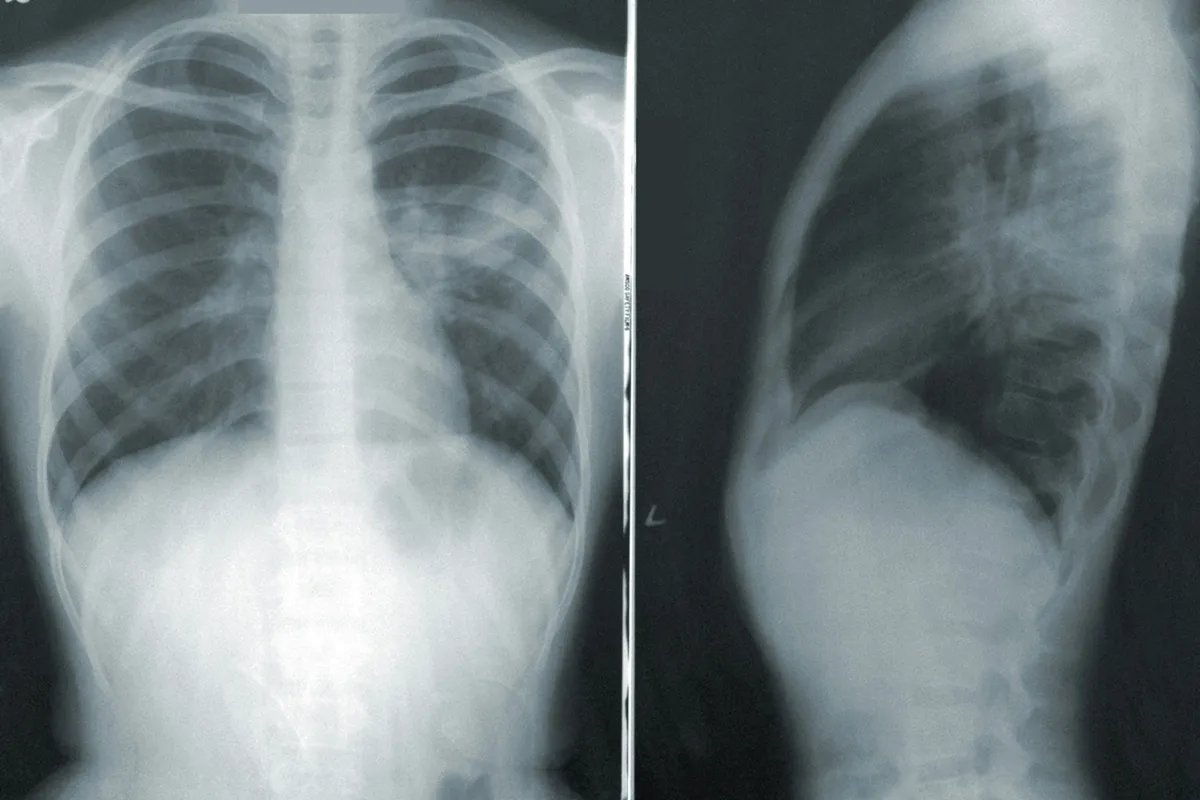

흡연은 암, 심혈관질환, 만성폐질환의 주요 원인이다.

금연, 흡연은 암, 심혈관질환, 만성폐질환의 주요 원인이다